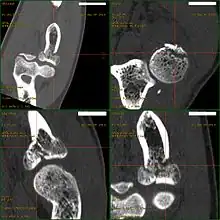

CT scan demonstrating the Mason type III radial head fracture